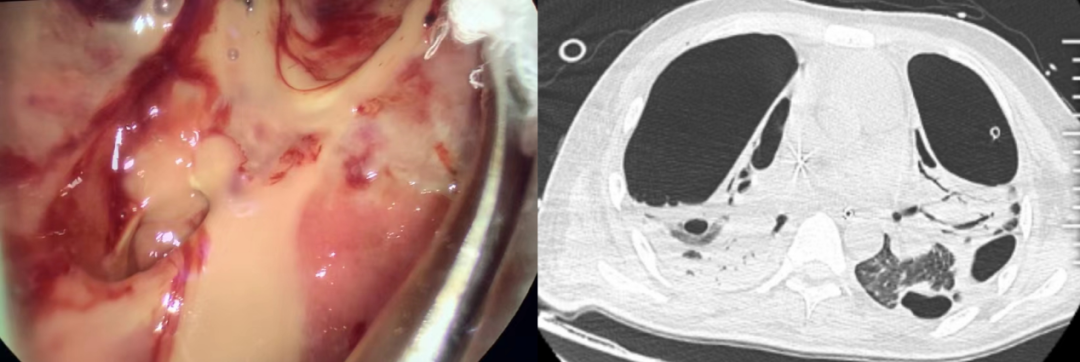

2022年,陳靜瑜會診一名20歲的大一新生。左圖為胸腔鏡下膿胸肺不張。/受訪者提供